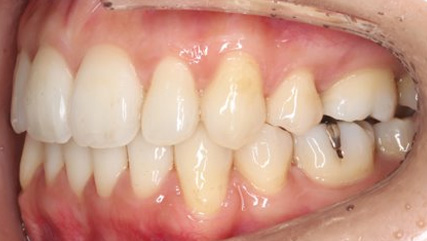

上顎前突といわれ、上顎の前歯が唇側に出ている状態を言います。

前歯が出ることで見た目の問題もありますが、口を閉じることができない、口呼吸をしてしまう、外傷などのリスクがあります。

日本人に叢生の次に多い不正咬合と言われており、自然に治ることはありません。また上の前歯が出ている事だけが気になるかもしれませんが、多くの場合、上顎の奥歯の位置に問題があることが多く、部分矯正でなく根本的な治療をした方がいい場合が殆どです。

口を閉じることができないことで、鼻呼吸でなく口呼吸をしてしまい、結果、成長期の場合顎の骨の成長を邪魔してしまうとも言われております。その他、口呼吸はアトピーなどを含むアレルギー症状の悪化、風邪を含むウイルス性の感染症にかかりやすいなどのリスクも増大してしまいます。

歯並びだけでなく全身への影響も多い為、早期の治療をおすすめ致します。